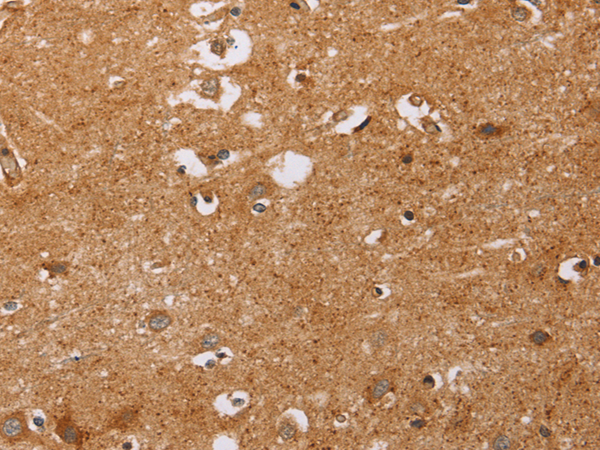

分类: 科研抗体货号: P11628别名: LEC; LMC; NCC4; CKb12; HCC-4; LCC-1; Mtn-1; NCC-4; SCYL4; ILINCK; SCYA16应用: WB,IHC反应种属: Human

分类: 科研抗体货号: P11640别名: T10应用: WB,IHC反应种属: Human

分类: 科研抗体货号: P11626别名: KRS1; MST2/KRS2; MST1; YSK3; TIIAC应用: WB,IHC反应种属: Human, Mouse

分类: 科研抗体货号: P11638别名: CD327; CD33L; OBBP1; CD33L1; CD33L2; CDW327应用: WB,IHC反应种属: Human

分类: 科研抗体货号: P11636别名: LY94; CD335; NKP46; NK-p46应用: WB,IHC反应种属: Human, Mouse

分类: 科研抗体货号: P11664别名: CIB; CIBP; KIP1; PRKDCIP; SIP2-28应用: IHC反应种属: Human, Mouse, Rat

分类: 科研抗体货号: P11634别名: CD30; Ki-1; D1S166E应用: IHC反应种属: Human